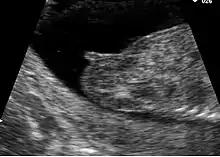

Pregnancy

In pregnancy, the vulva and vagina take on a bluish coloring due to venous congestion. This appears between the eighth and twelfth week and continues to darken as the pregnancy continues.[37] Estrogen is produced in large quantities during pregnancy and this causes the vulva to become enlarged. The vaginal opening and the vagina are also enlarged.[52] After childbirth, a vaginal discharge known as lochia is produced and continues for about ten days.[52]